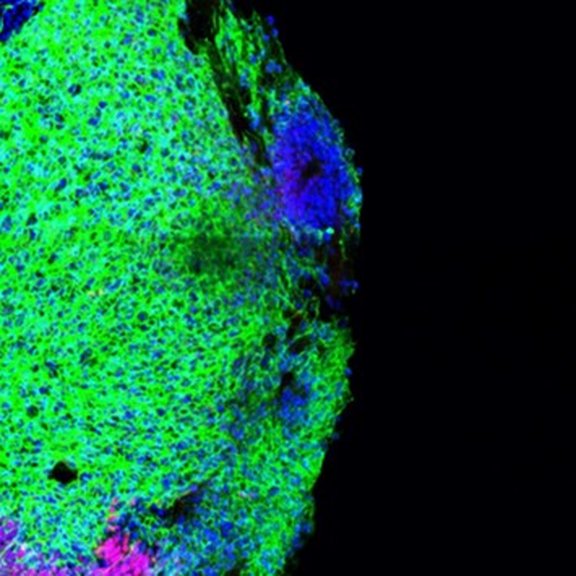

Human Brain Development

Research